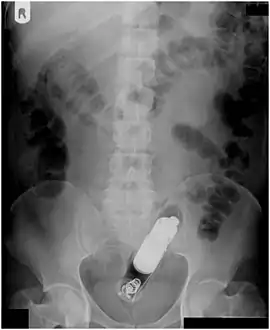

Rectal foreign body

Radiograph of a male abdomen with a vibrator inside the rectum

Usually, several radiological images are recorded in order to pinpoint the precise place and depth of the foreign body. This is usually done by X-ray. Foreign bodies made from low-contrast material (e.g. plastics) may necessitate medical ultrasound or a CT scan.[29] Magnetic resonance imaging is contraindicated, especially if the foreign body is unknown. Foreign rectal bodies may penetrate deep into the colon, in certain circumstances up to the right colic flexure.[10]